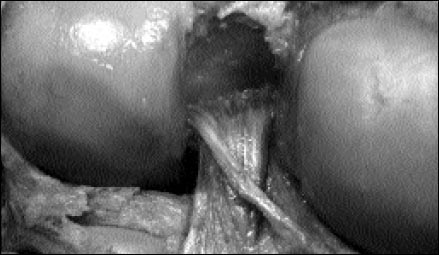

Figura 2: Vista posterior de rodilla derecha. Nótese el LMFp discurrientdo en forma oblicua al LCP

El ligamento meniscofemoral posterior (Wrisberg) estuvo presente en 28 de las 40 rodillas estudiadas (70%) (Fig.2). Tiene un origen común con el ligamento de Humphry y corre por detrás del LCP insertándose en el fémur, posterior e inferior al ligamento cruzado posterior. En 12 rodillas el LMFp estuvo ausente (30%) (Fig.3).